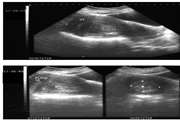

In this paper, we proposed an automatic method for segmentation of uterus in MRIs

Uterine segmentation and volume measurement in uterine fibroid patients’ MRI using fuzzy C mean algorithm and morphological operations

In this paper, we will introduce a new method for uterine segmentation in T1W and enhanced T1W magnetic resonance (MR) images in a group of fibroid patients candidated for UAE in order to make a reliable tool for uterine volumetry.